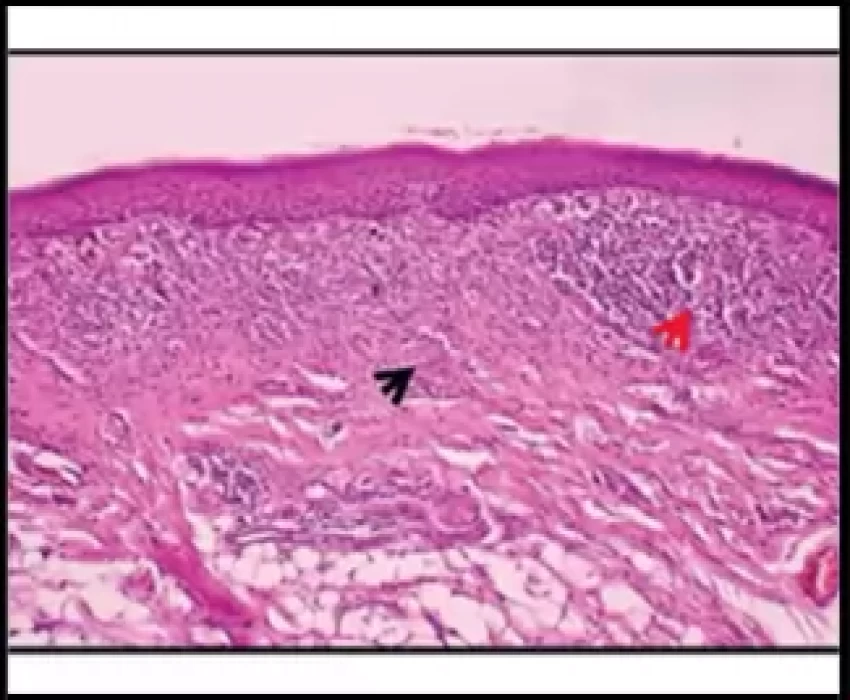

Oral Submucous Fibrosis (OSMF) is a precancerous condition and is mainly associated with the chewing of areca nut. This study was undertaken to correlate the etiological factors (duration, frequency, style and chewing habit) associated with OSMF with clinical grading and histological staging. The widespread habit of chewing gutkha plays a major role in the development of Oral Submucous Fibrosis than any other habit. The duration and frequency of its use and type of areca nut product has effect on the incidence and severity of OSMF.

The widespread habit of chewing gutkha has major role in the occurrence and severity of OSMF, especially in younger age group. The occurrence of OSMF in gutkha chewers is faster and more severe as compared to any other forms of areca nut products. The relative risk of disease increased with frequency and manner of chewing which conclude that the daily consumption rate appears to be relatively significant with respect to risk than the lifelong duration of habit. The histological grade should be considered as the gold standard in deciding the treatment plan and routine surveillance programme should be carried out in order to stop this perilous habit.